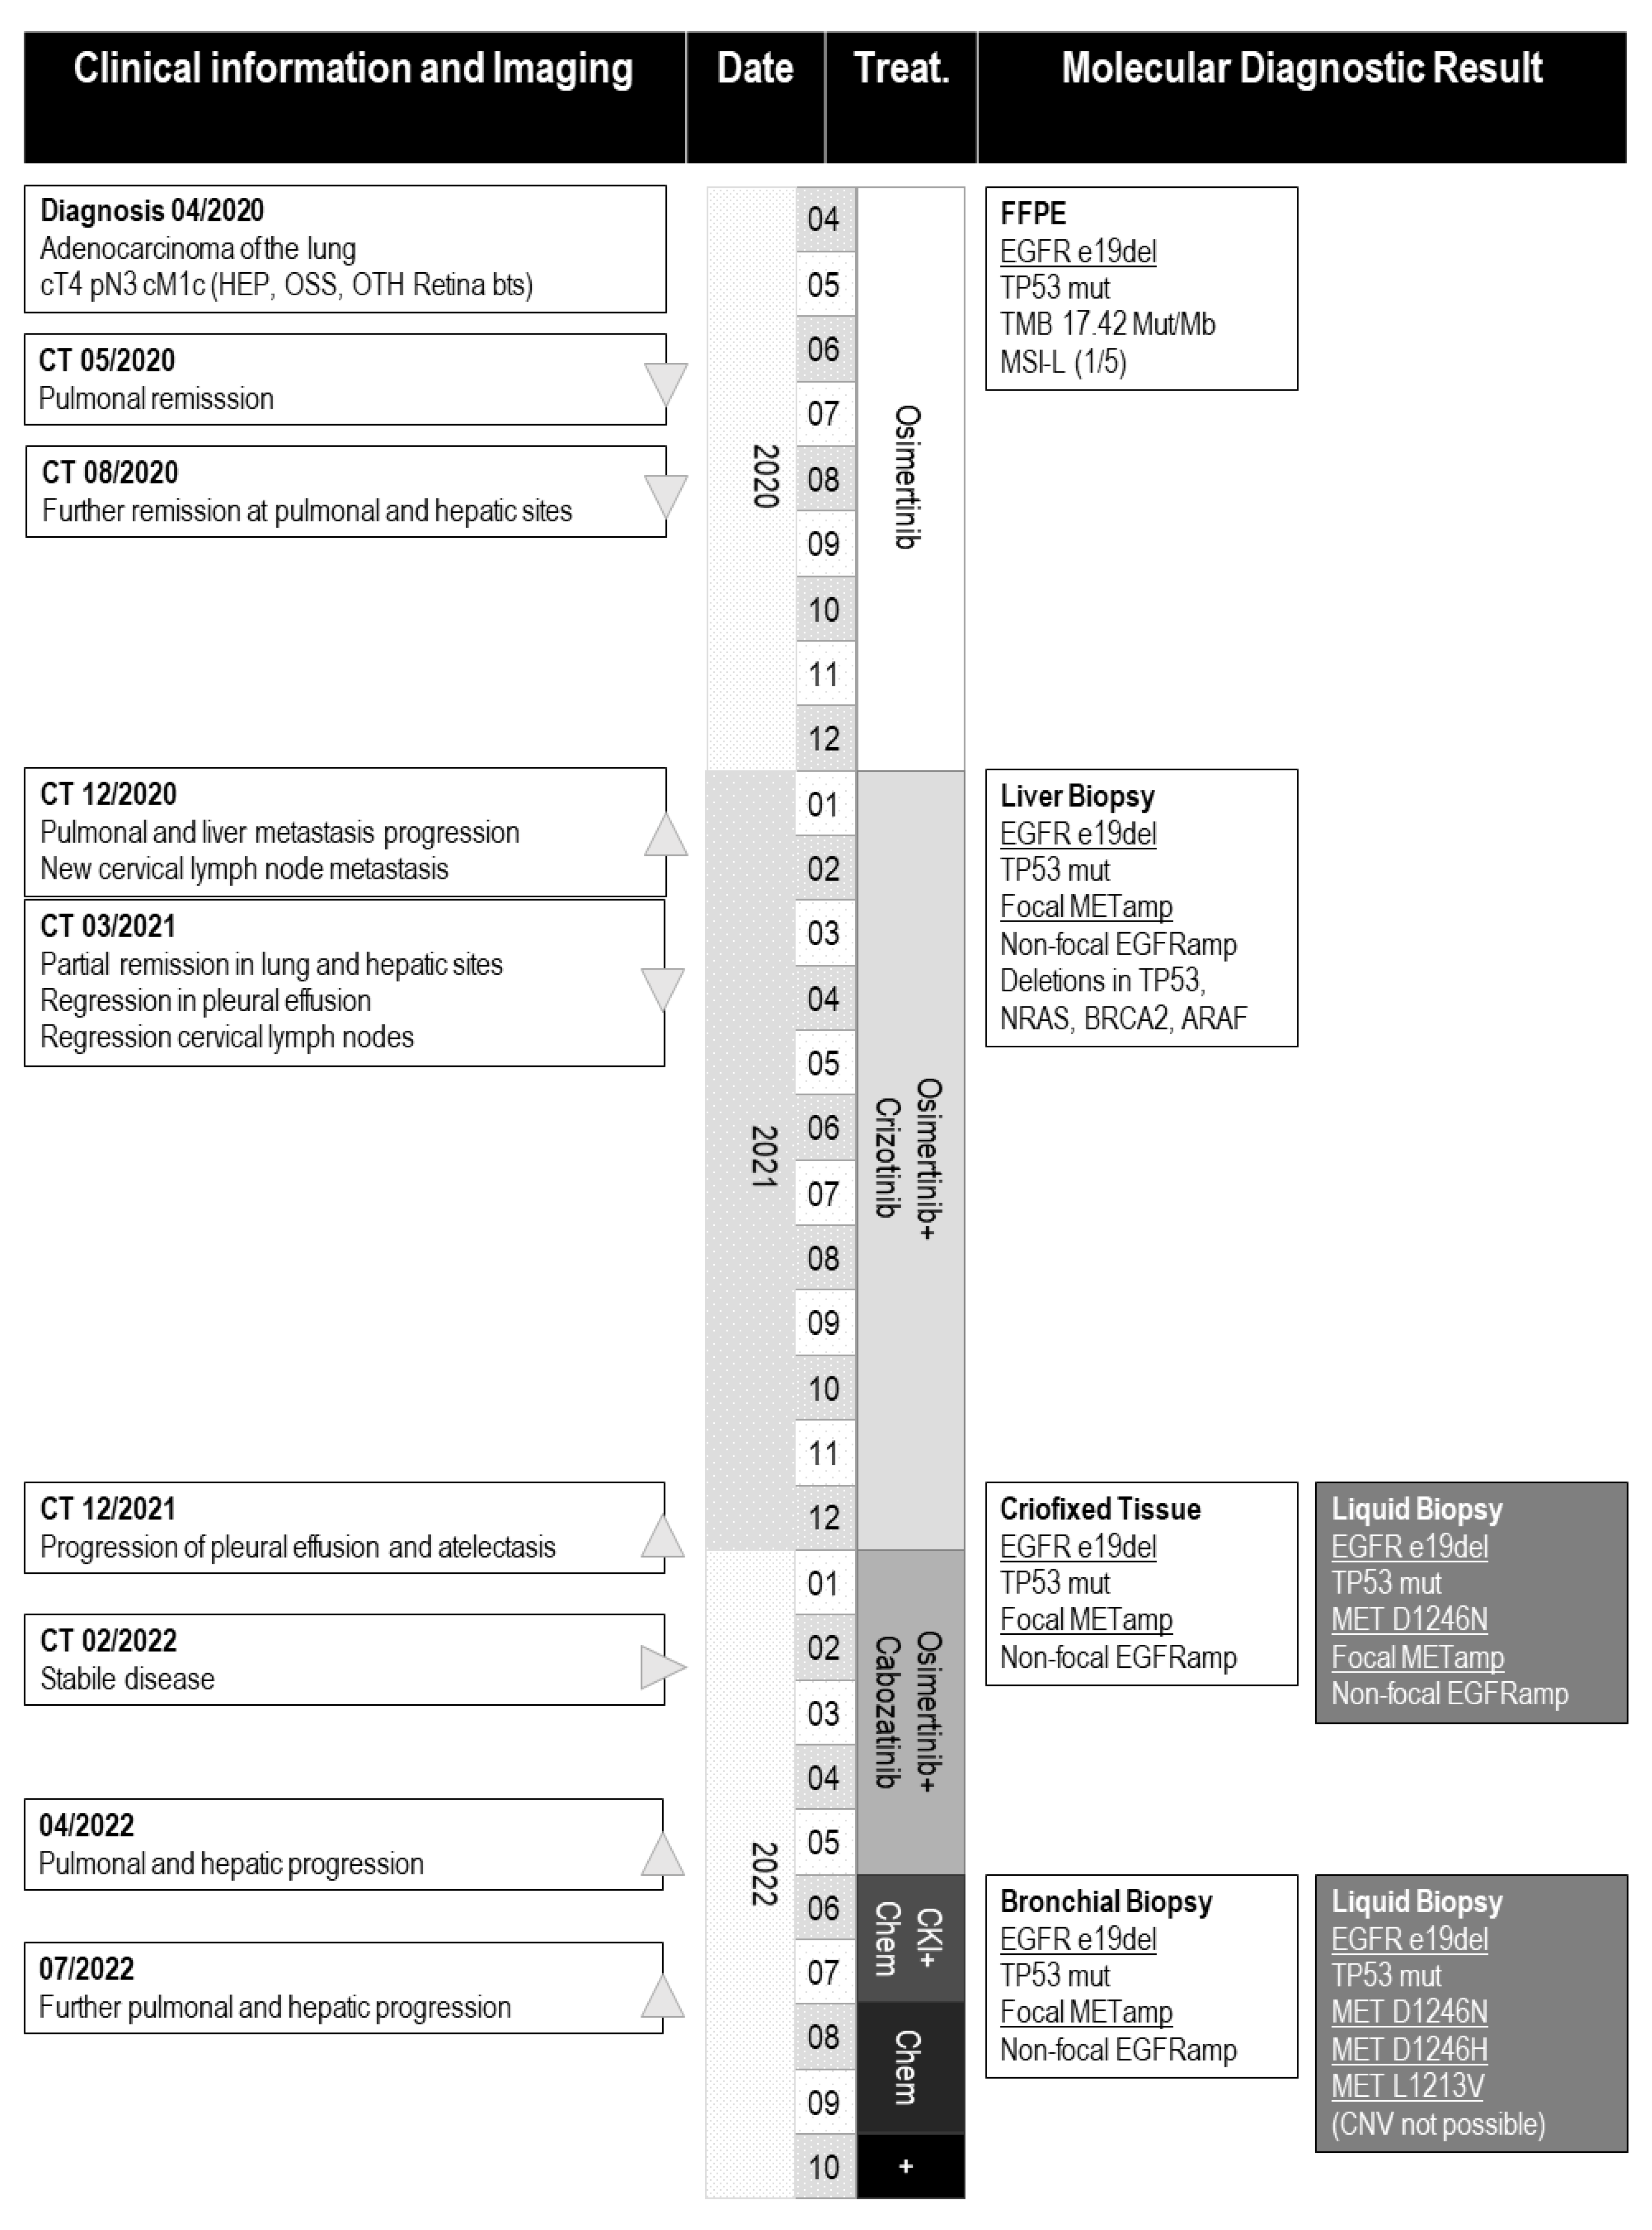

2. Case Presentation